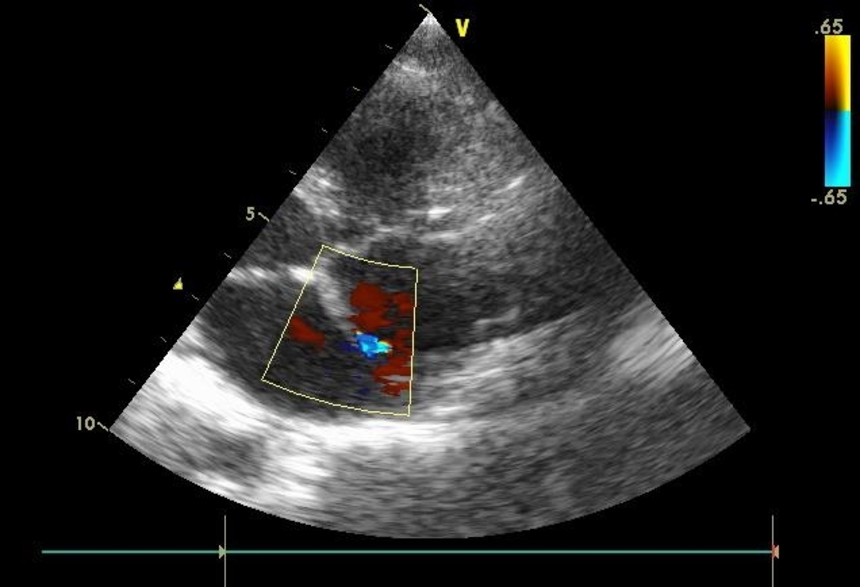

«Золотым стандартом» определения врожденных аномалий сердца кардиологи называют эхокардиографию.

Врач ультразвуковой диагностики судит о наличии открытого овального отверстия по следующим критериям:

- двухмерная эхокардиография: перерыв сигнала от перегородки в месте локализации овальной ямки, постепенное клиновидное утончение к краям дефекта, отсутствие перегрузки объемом правой половины сердца, парадоксальные движения преграды между предсердиями;

- допплер-эхокардиография: турбулентные потоки крови в месте расположения овального окна, показатели кровотока в правом желудочке и легочной артерии соответствуют норме.

ЭхоКГ

Двухмерная эхокардиограмма показывает диаметр открытого окна и движение клапана, она поможет отличить эту патологию от других пороков сердца. Этот метод помогает выявлять наличие турбулентного потока крови, его объема и скорости. Для диагностики ООО это самый информативный способ.

ЭхоКГ при открытом овальном окне